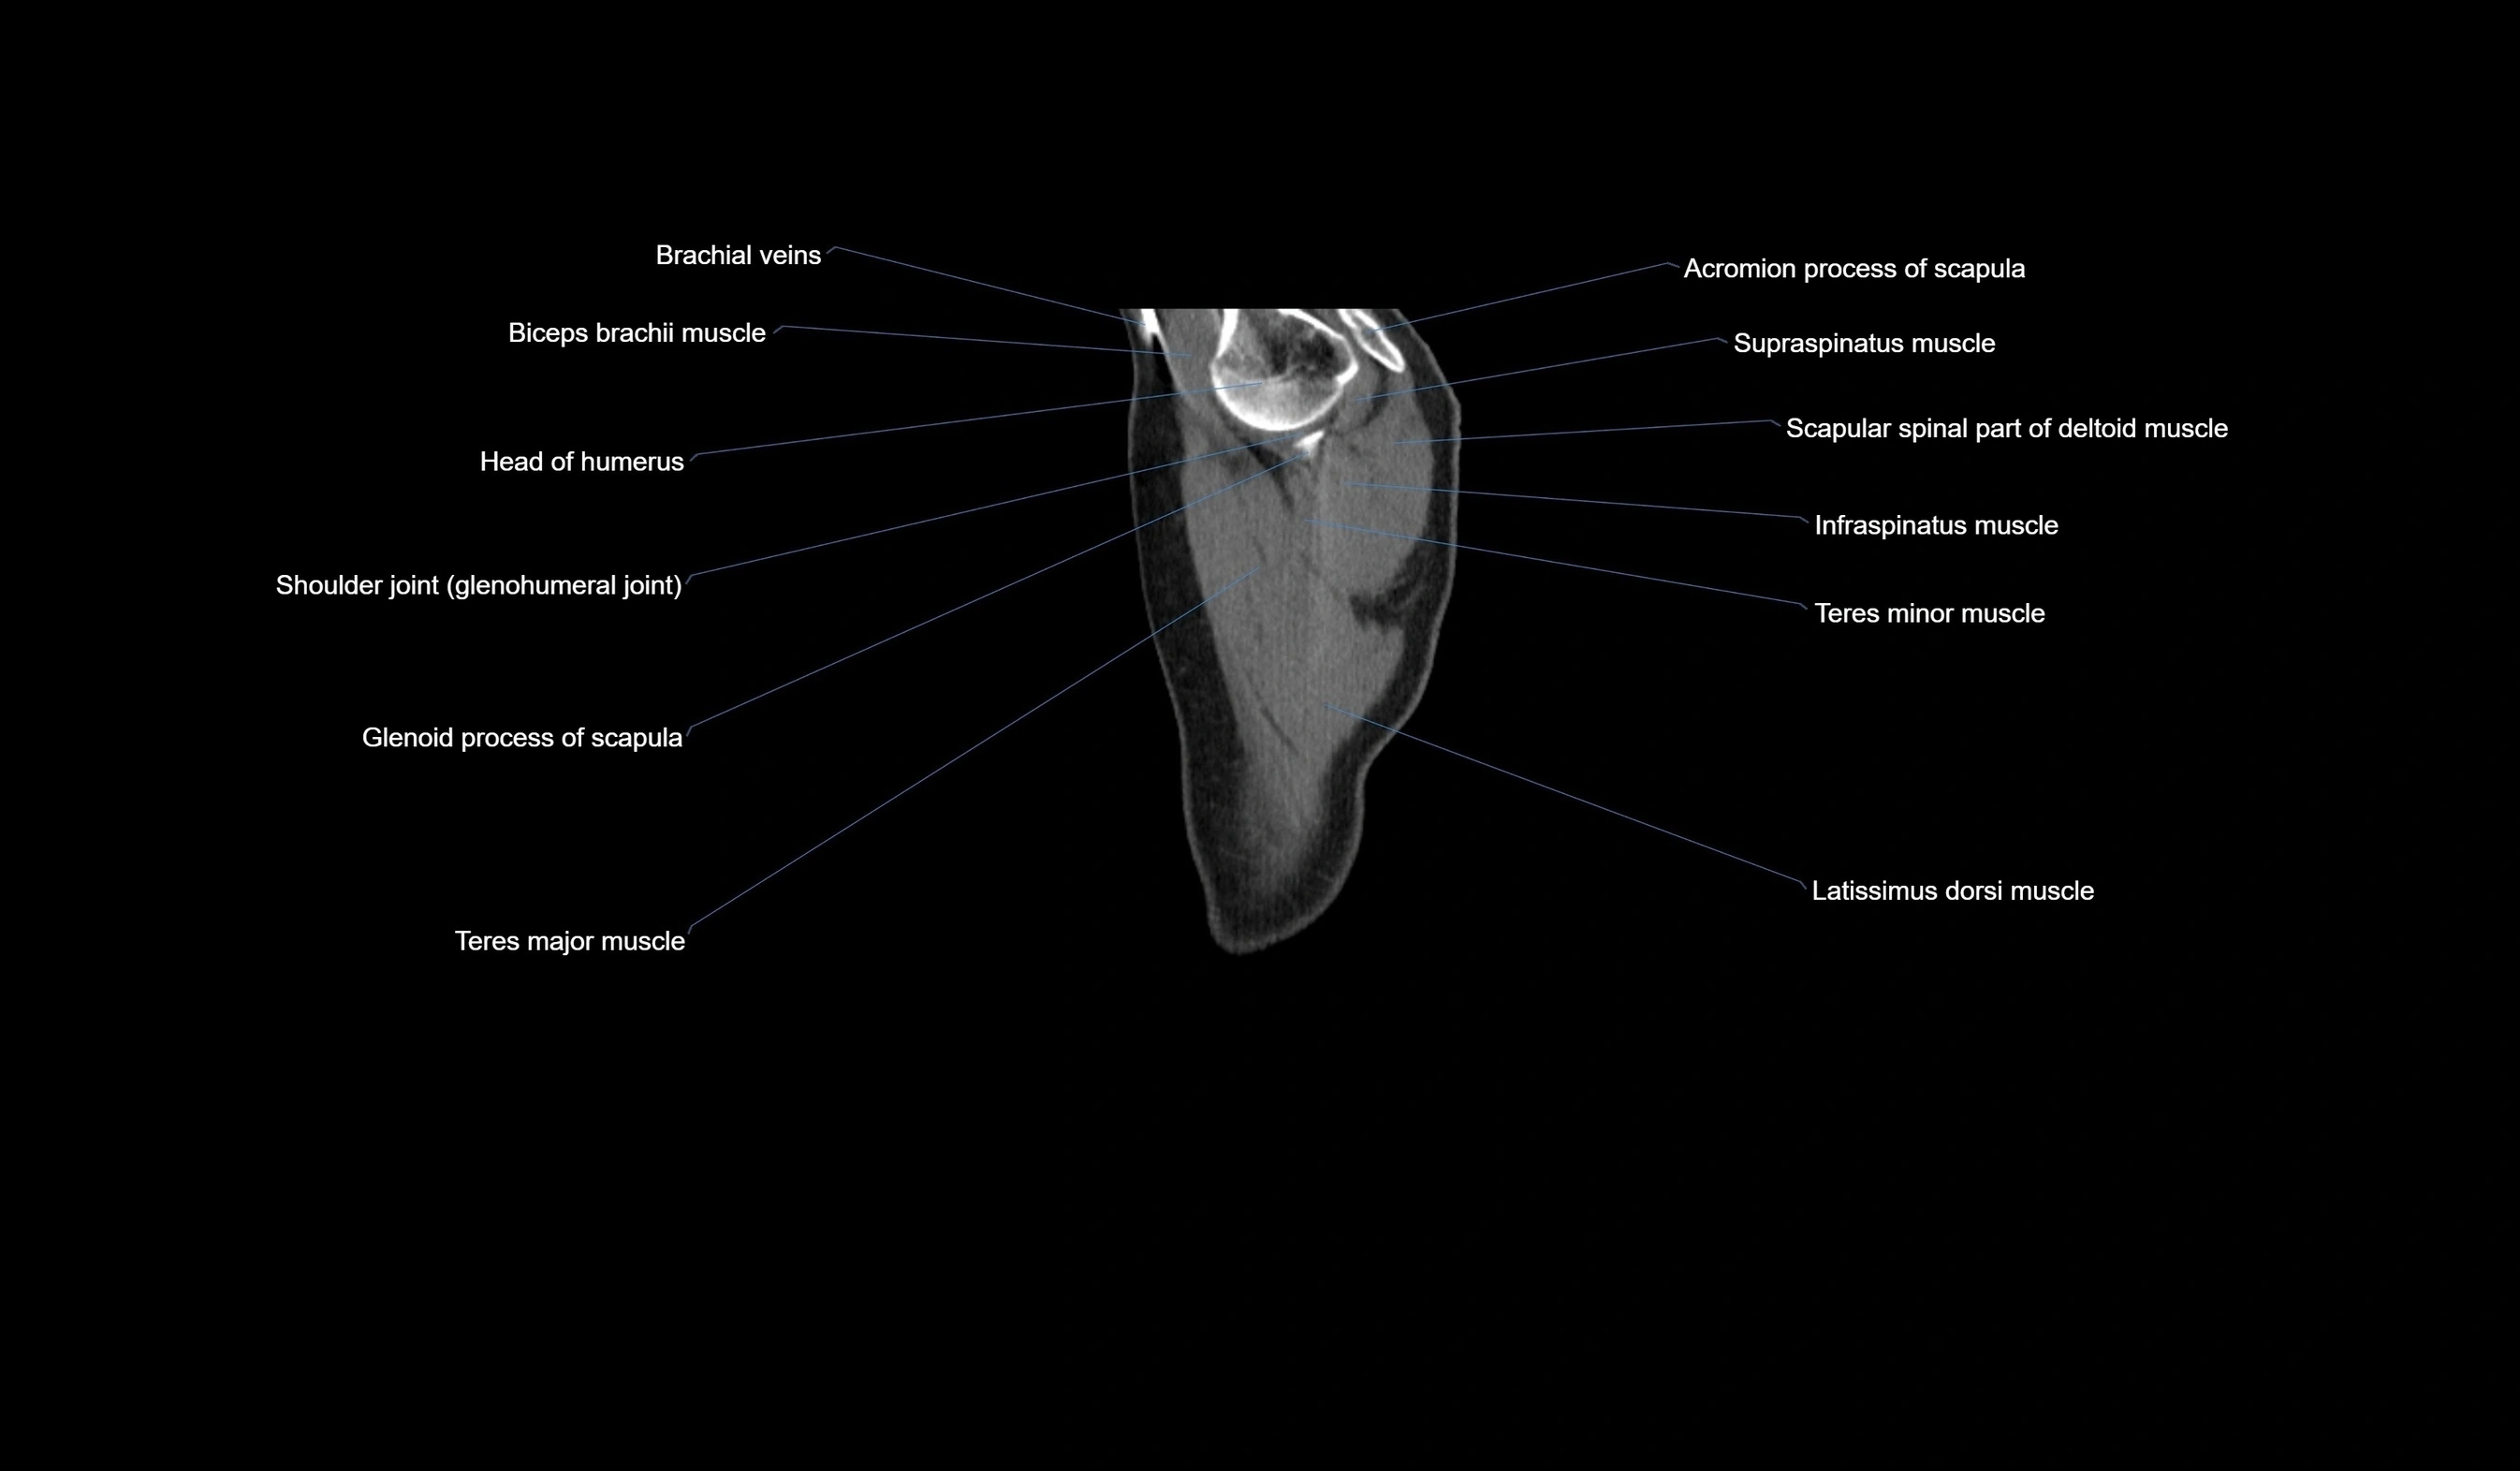

MRI images